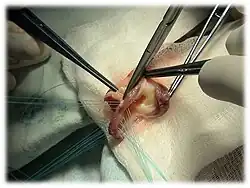

Используются в сердечно-сосудистой хирургии в качестве пластического материала для замены клапанов сердца и/или фрагментов сосудов и/или шунтирования сосудов сердечно-сосудистой системы, для коррекции врожденных и приобретенных пороков сердца.

Клапан лёгочной артерии (пульмональный) часто используется у детей с врождёнными пороками сердца, в то время как аортальный — при разрушении аортального клапана при воспалительном процессе для его замены.

Существует операция Росса, при которой для протезирования аортального клапана используется собственный клапан легочной артерии, на место которого имплантируется гомографт и операция Росса II, при которой легочный аутографт используется для протезирования митрального клапана, на место которого имплантируется гомографт.